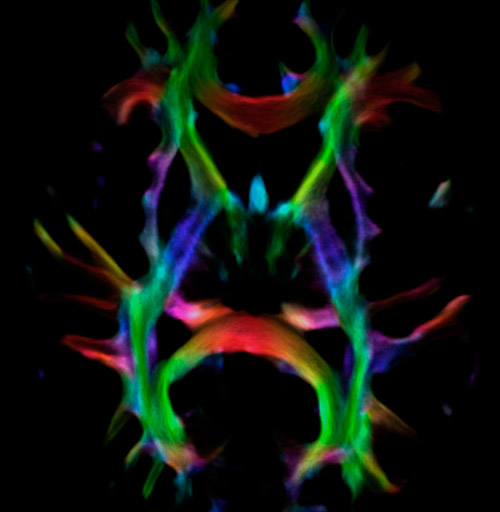

DEC TDI

Super-resolution directionally encoded color track-density imaging

UVM research fiber super resolution

UVM research super resolution